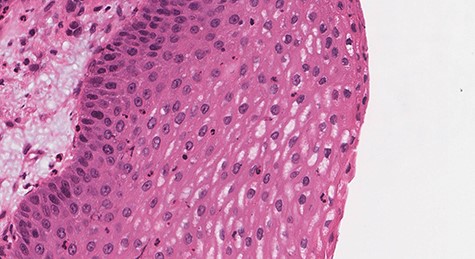

Histologic sections show an endophytic (inverted) pattern that grows downward into the underlying stroma (Fig. 4). The epithelium consists of hyperplastic squamous epithelium (Fig. 5) and ciliated columnar cells admixed with scattered mucocyets (goblet cells) (Fig. 6). The cells have a bland appearance and uniform small nuclei. No cytologic atypia, increased mitotic activity or necrosis seen. Mixed inflammatory cells are dispersed within the epithelium and stroma.

![Section of IP (hematoxylin and eosin [H&E] stain; ×29).](https://oupdevcdn.silverchair-staging.com/oup/backfile/Content_public/Journal/jscr/2020/8/10.1093_jscr_rjaa180/1/m_rjaa180f4.jpeg?Expires=1770025183&Signature=GzL9MbKsK6--L8BpaFn8KbPB1vTqJXt8JLmBi40Al~aNVXHBcE3WBdMSNWceP4etM3oRO68BydJcpTLlYl5cgweZ8DEIzjSbjtdjLGkWsf71cqBx8tP3XyTG5ovxrAyY~3pLYTY4PaM40fvVDaQlr9WMcDpaNJH0~9XEoPBGlgiv3lkp~t-yXGUUHt5RTCWK3fn6LL63As6R31I8tk7x-SubFeXlspgLcssufoygDcYrzVLJDLTKUVrZzPV~B~ehrqSpeZn-nFV2aF17tnDG9fhSNfRJPT6uXqs~0dIEvuoQdXQTt1TmLV1gfn0lHYzI585I4MXrJiuEc4H~HSNbHA__&Key-Pair-Id=APKAIYYTVHKX7JZB5EAA)